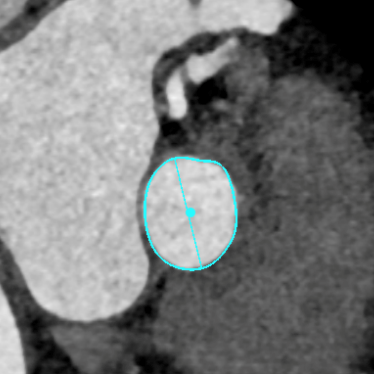

CT测量

主动脉根部CT测量

瓣环周长:68.1mm

最长直径:23.3mm

LVOT周长:69.0mm

最长直径:23.8mm

左冠开口高度:8.7mm

右冠开口高度:8.4mm